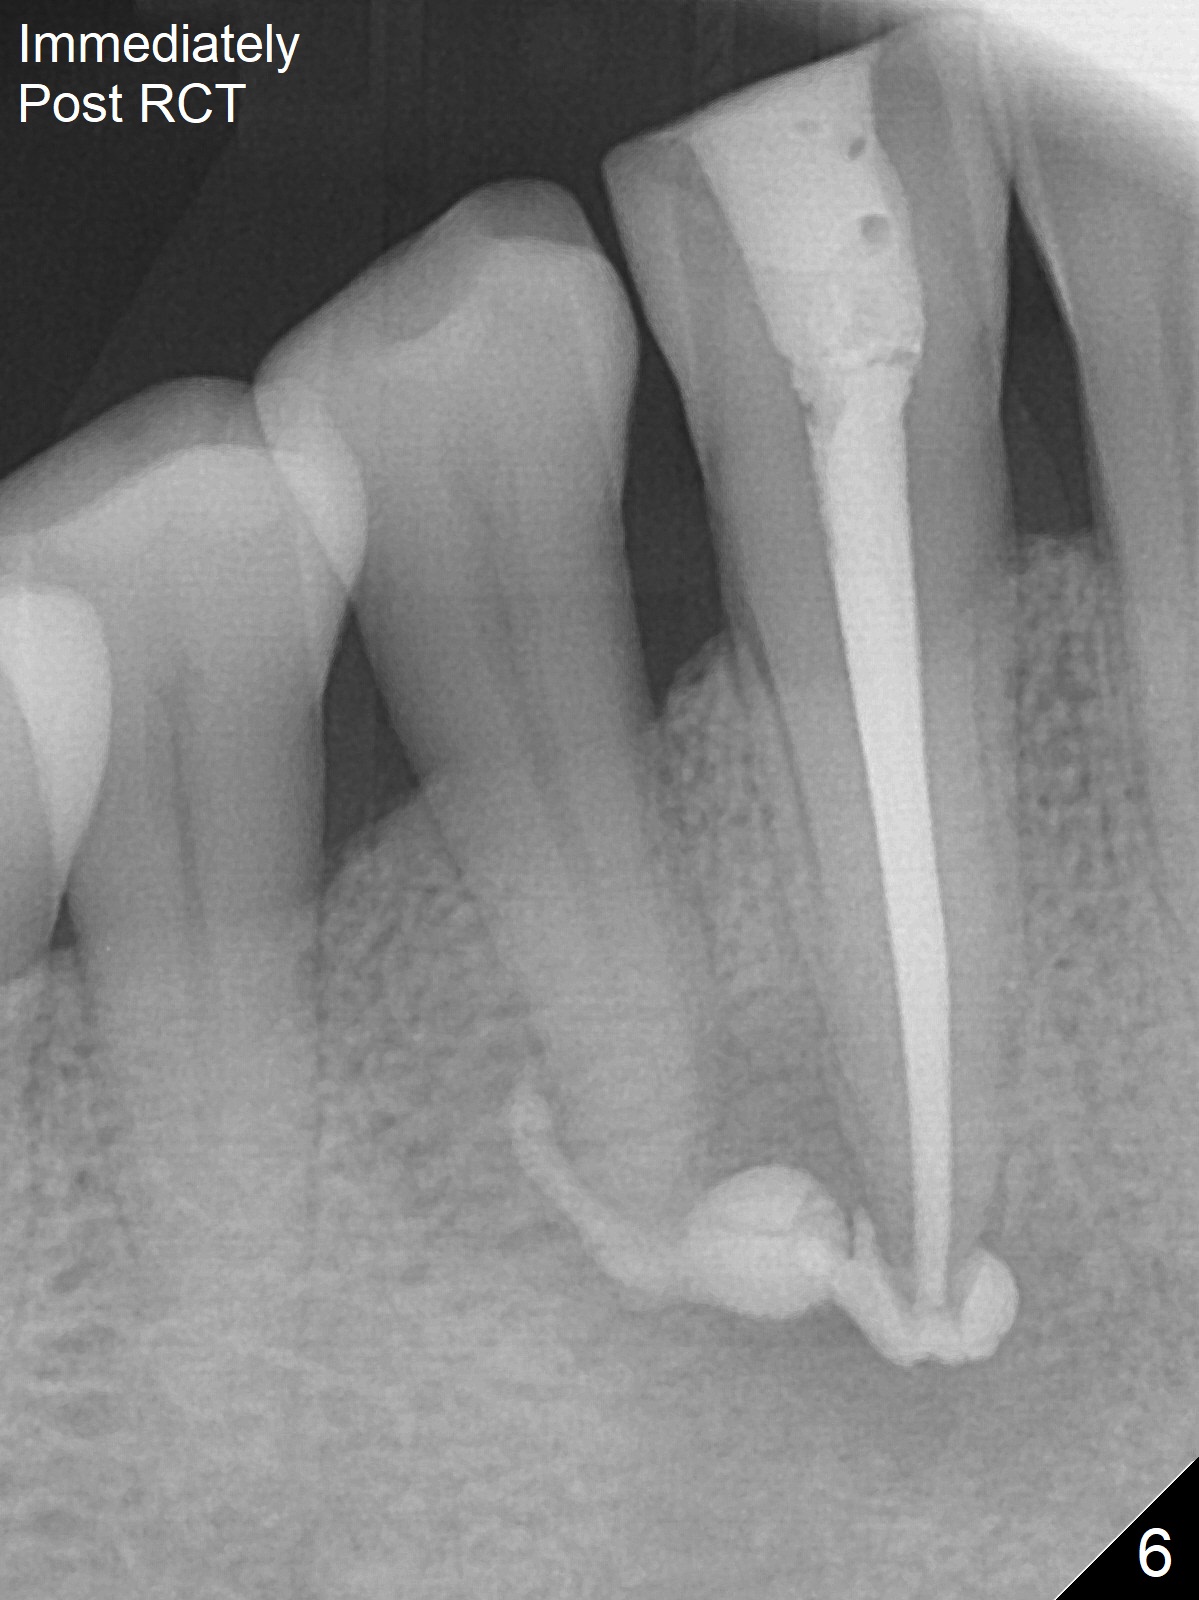

The patient reports that the fistula disappears after initial RCT at #27, but it seems to re-appear 1 month post canal debridement (Fig.5 >). After repeated debridement with #40 hand file at 23 mm, apply Endo Sequence BioCeramic Sealer and insert GT 40/.08 master cone with black carrier (Fig.6). One hour later, the patient returns with re-appearance of the fistula (Fig.7). Following local anesthesia, poking the fistula leads to sealer escape (Fig.8). After debridement of the fistula until the bone, PA is retaken (Fig.9). A crown was made in China; mesial radiolucency starts (Fig.10). The tooth remains asymptomatic 1 year 5 months postop (Fig.11). There is a lingual fistula with enlarged mesial radiolucency 2 years 3 months postop (Fig.12-14).